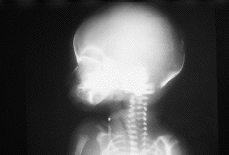

Se practica una radiografía postmortem que informa de la presencia de aire intestinal y pulmonar en las grandes vías aéreas, y de la ausencia de hemivértebras.

El informe autópsico es el siguiente: Feto hembra de treinta semanas de gestación, según peso y longitudes occipito-sacra y del pie, que presenta inmadurez visceral grado II, polimalformado, presentando anomalías faciales, hipoplasia pulmonar (índice peso corporal/peso pulmonar = 0,007), surco simiesco bilateral, bazo supernumerario (0,3 cm) y quiste simple subcapsular hepático (0,2 cm). Las anomalías faciales son las siguientes: Asimetría del tercio facial inferior, con hipoplasia mandibular y de zigoma derechos, microotia derecha con implantación baja de conducto auditivo externo, discreto hipertelorismo, atresia de coanas bilateral, anquiloglosia y paladar ojival con fisura palatina mucosa (ver imágenes adjuntas).

| Figura 4. |